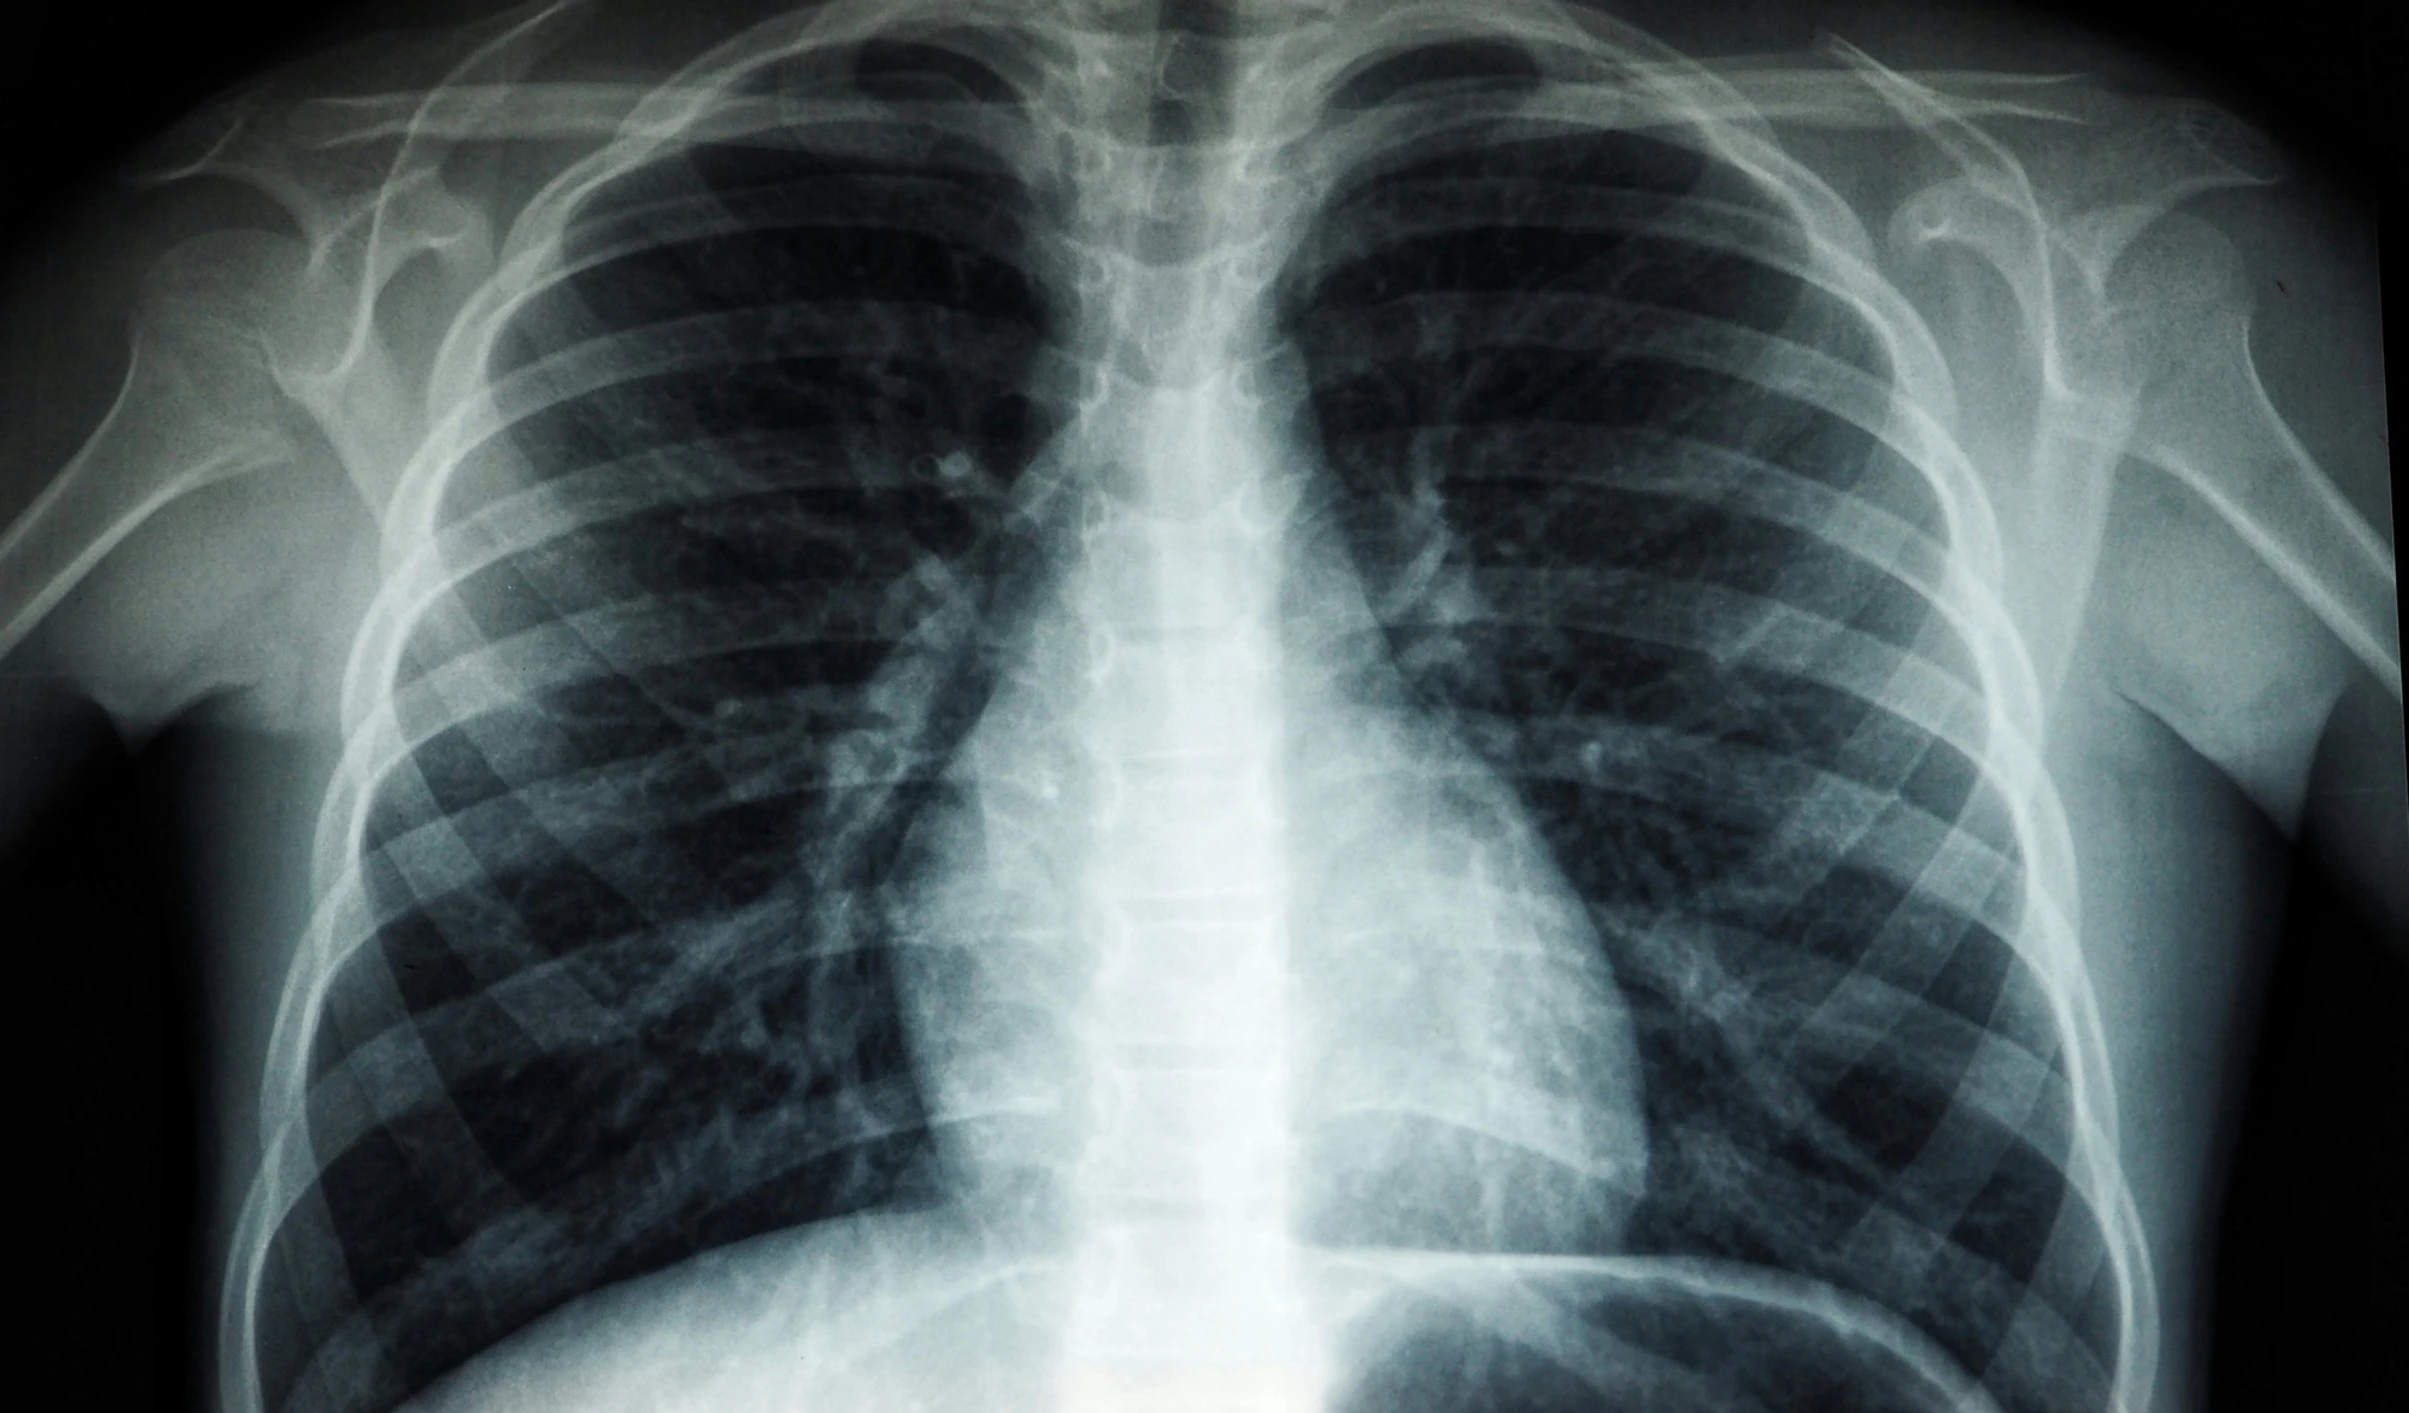

The World Health Organisation (WHO) urged governments in the Western Pacific region to accelerate country-led action to transform tuberculosis care, decentralize services and scale up innovation to end one of the deadliest infectious killers in the region and around the world.

In 2024, an estimated 2.9 million people were affected by TB across the Western Pacific region, with Indonesia, the Philippines and China among the world’s top five high-burden countries.